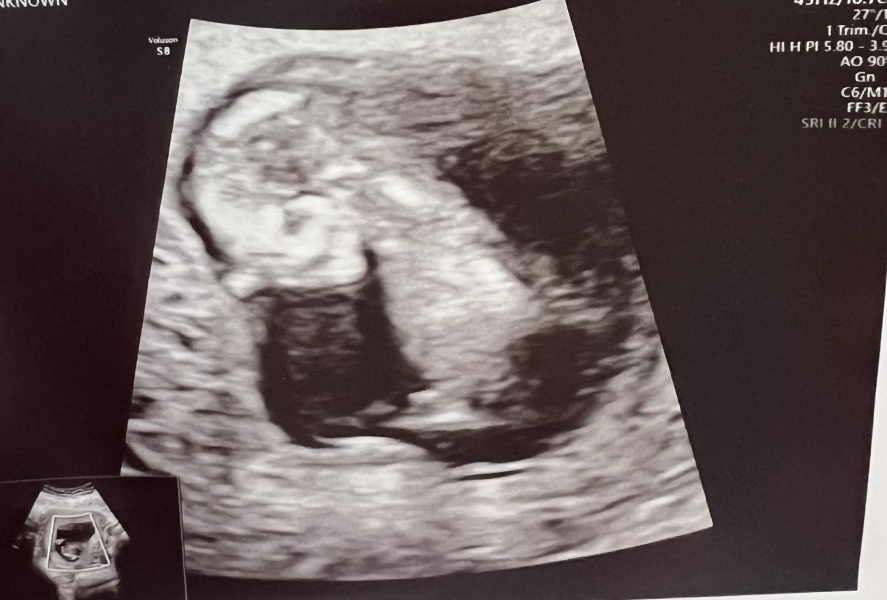

Nub theory prediction

Hiya I’m a first time mum, not too sure what the nub theory is, but can anyone help me out with guesses?

I can't see a nub on your scan photo, do you have any other pics?

Your scan also needs to be 12 weeks min as the nub can still change before then